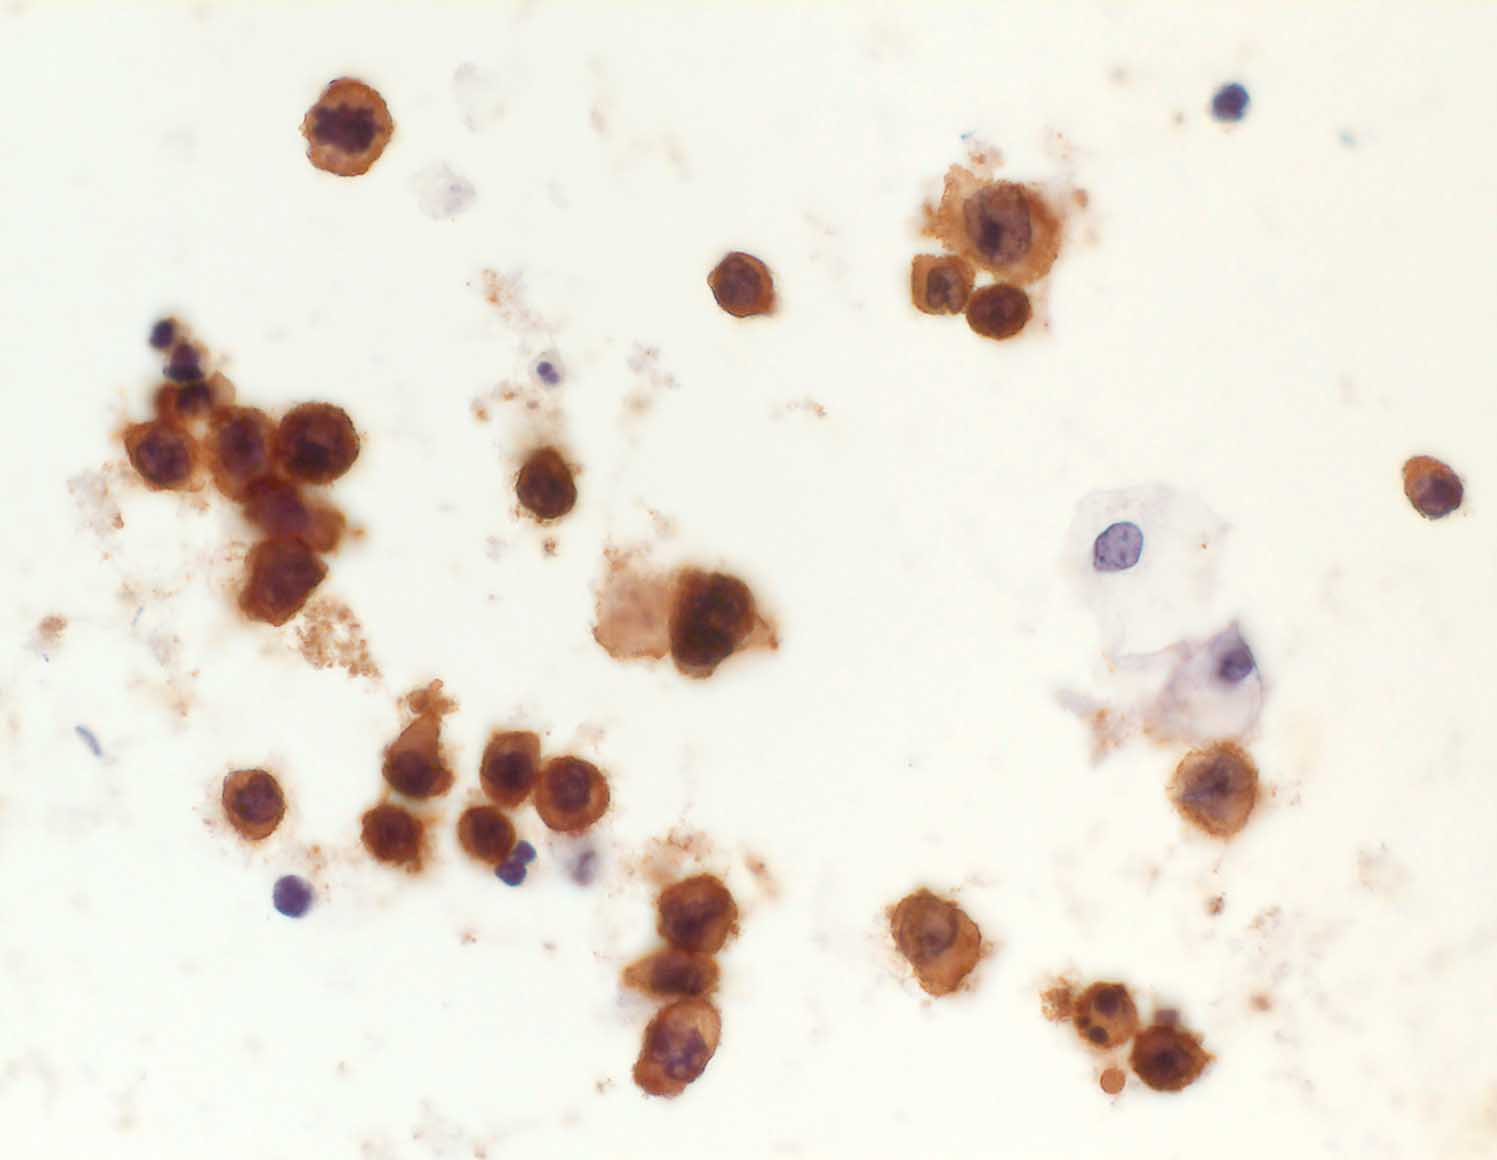

pit/ Diffuses grosszelliges B-Zell Lymphom

Diffuses grosszelliges B-Zell Lymphom

Diffuse grosszellige B-Zell Lymphome treten nicht selten in extranodalen Lokalisationen auf und können klinisch als Karzinom fehlgedeutet werden. Bei ungewöhnlicher Zytomorphologie eines malignen Tumors sollte deshalb immer auch an die Möglichkeit eines nicht epithelialen Tumors gedacht und der Befund mittels Immunzytochemie weiter abgeklärt werden. Zur Unterscheidung eines Lymphoms von einem epithelialen Tumor eignen sich der panleukozytäre Marker CD45 (LCA) und ein Panzytokeratinmarker oder BerEP4.

Beim ersten Fall handelt es sich um ein primär extranodales Lymphom des Nierenbeckens, das im Urin diagnostiziert wurde. Beim zweiten Fall handelt es sich um ein primär extranodales Lymphom im Bereich der Nebenniere mit Nachweis von Lymphomzellen im Aszites.